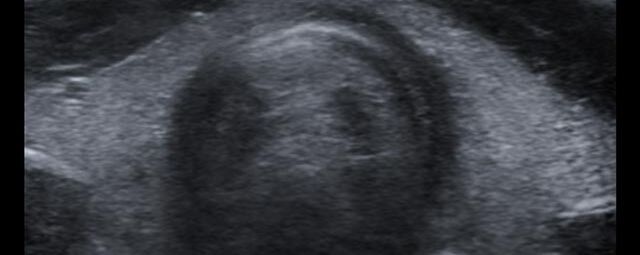

Die Sonographie ist ein bildgebendes Verfahren in der medizinischen Diagnostik, das mit Ultraschallwellen arbeitet. Ultraschall ist Schall mit einer Frequenz oberhalb der menschlichen Hörgrenze. Im medizinischen Bereich werden je nach Körperregion Ultraschallwellen in einem Frequenzbereich von ca. 3,5 – 18 Mhz verwendet. Die körpernahe Ultraschallsonde sendet durch einen piezoelektrischen Effekt kurze Schallwellenimpulse in den Körper. Ultraschall-Gel stellt den Kontakt zwischen Sonde und Körper her. Je nach Gewebeart werden diese Schallwellen im Körper unterschiedlich stark reflektiert. Anhand des zurückgesendeten Schallmusters kann das Ultraschallgerät Schnittbilder berechnen, auf denen die Organe des Körpers nach krankhaften Veränderungen untersucht werden können.

Die Ultraschalluntersuchung ist eine nach derzeitigem medizinischem Kenntnisstand nebenwirkungsfreie Untersuchung. Da bei diesem Verfahren keine Röntgenstrahlung eingesetzt wird, eignet es sich insbesondere bei Kindern, Jugendlichen und jungen Erwachsenen sowie Schwangeren zur initialen Bildgebung. Bei erschwerten Untersuchungsbedingungen (z.B. durch erhöhtes Körpergewicht, Darmluft, Schmerzen oder krankhafte Veränderungen in tiefen Körperegionen, etc.) ist der Ultraschall unter Umständen stark eingeschränkt und muss durch andere Bildgebungen (CT, MRT) ersetzt bzw. ergänzt werden.